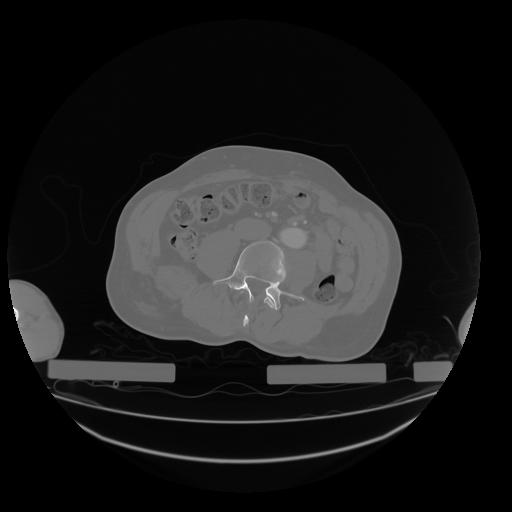

28 CUERPO,CE,Vol,2.0,CUERPO,,